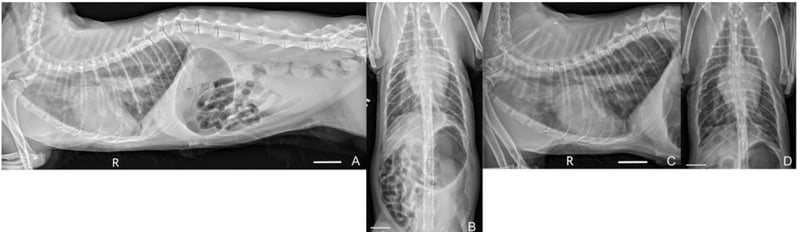

MusculoskeletalMusculoskeletal